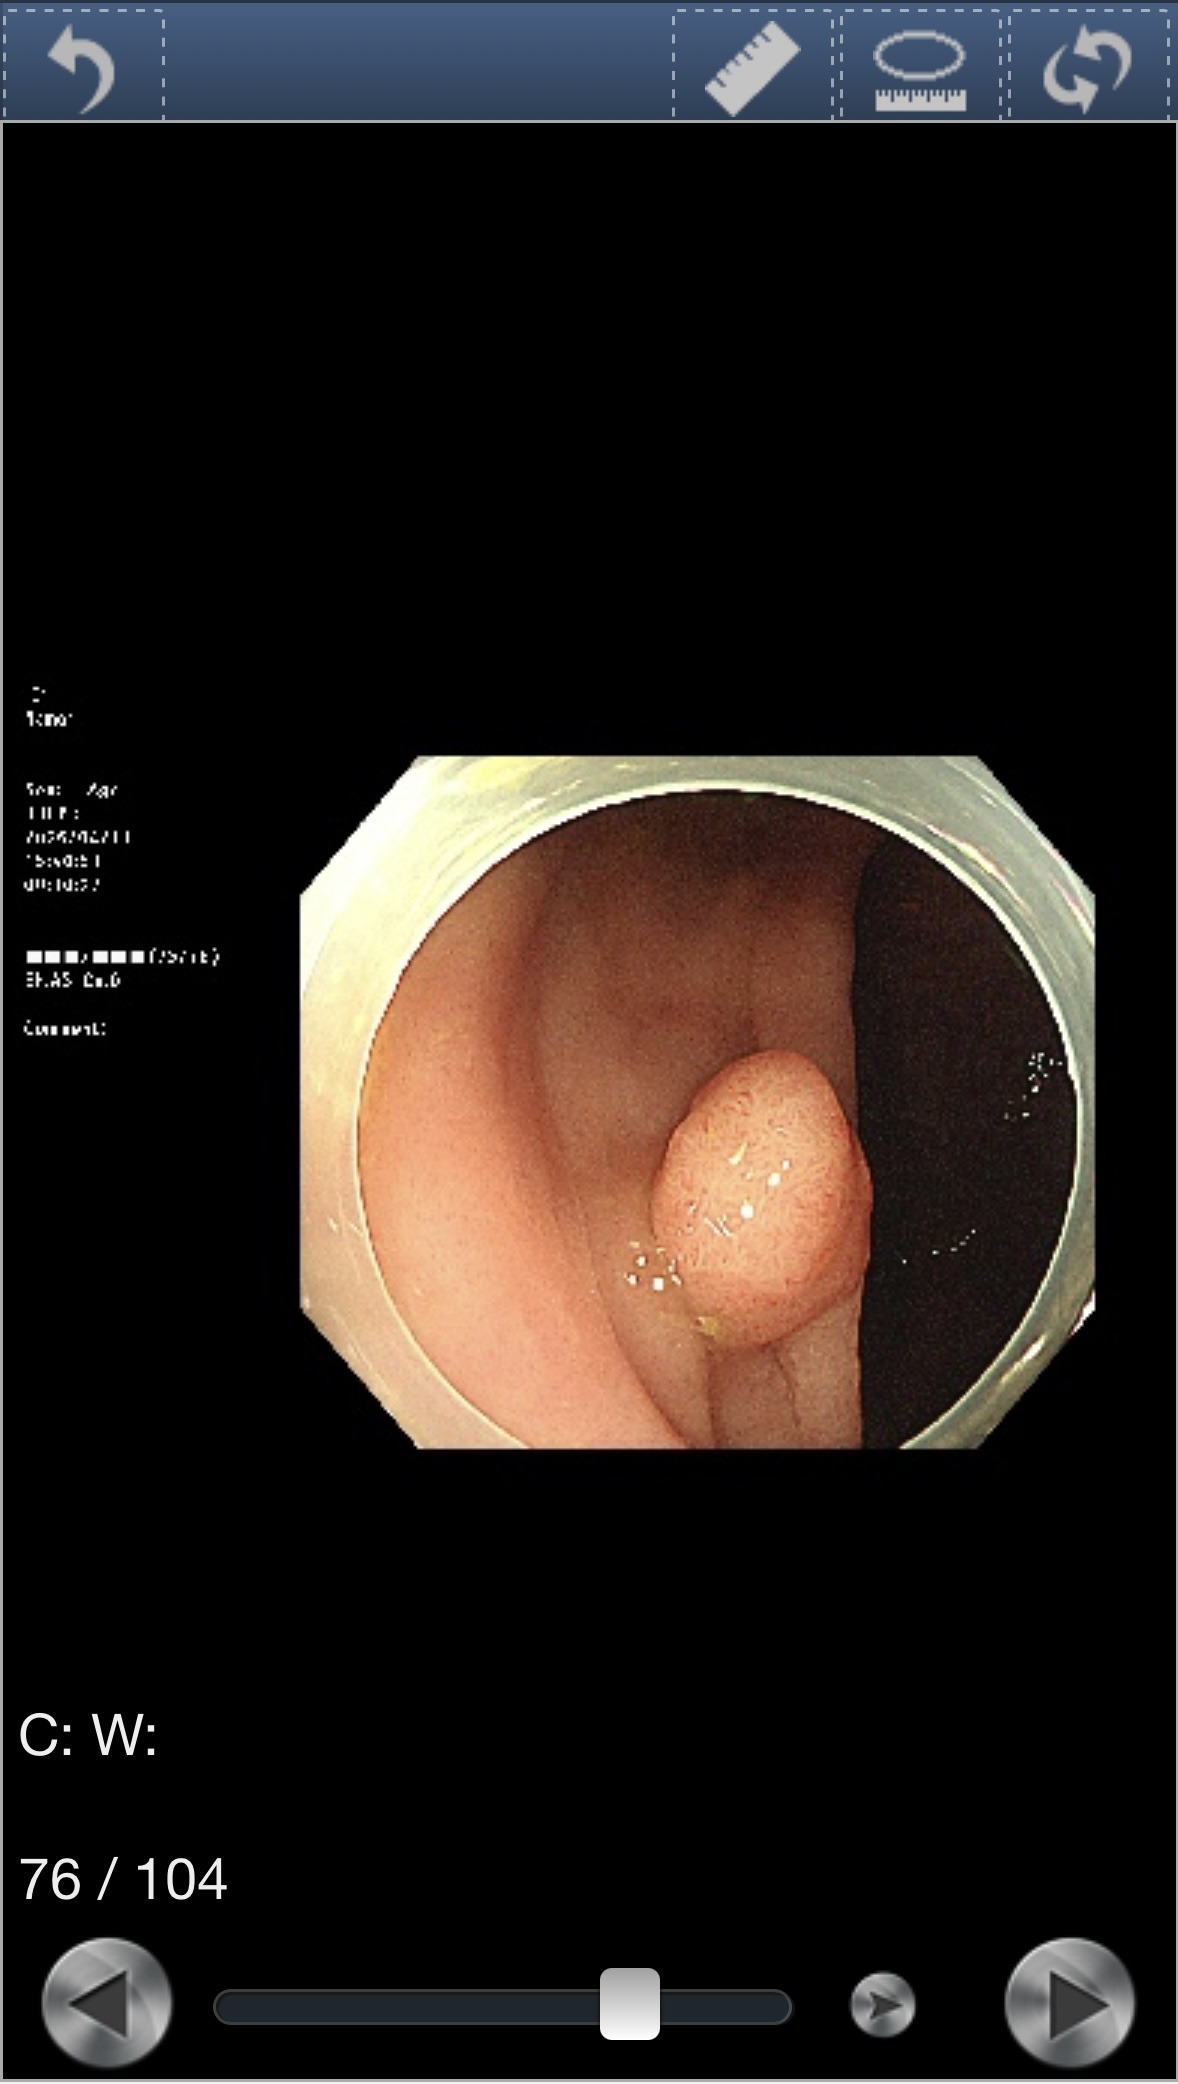

腸の中が綺麗になった状態で内視鏡を入れるのだが、

モニターに映った自分の腸管は鮮やかなピンク色だった。

下剤のおかげで粘膜がよく見える状態になっていた。

12mmポリープ発見・その場で切除

検査中にポリープが見つかった。サイズは12mm。

より精密に観察するため、色素を散布して輪郭を鮮明にした。

ドクターは「おそらく良性だと思います」と言ったが、念のため病理検査に出すため、その場で切除することになった。

切除後の粘膜はこうなる。